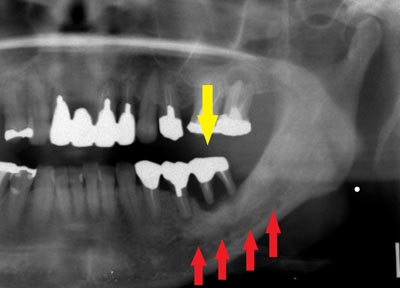

患者様の治療前のレントゲン写真です。写真の黄色矢印部の歯の周囲は、重度の歯周病で大きく歯槽骨が吸収されてしまっていました。そのため、写真の、赤色矢印で示す、下顎骨の中を通る神経までの距離がなく、インプラント埋入には、骨の高さが不足していました。

患者様の治療前のレントゲン写真です。写真の黄色矢印部の歯の周囲は、重度の歯周病で大きく歯槽骨が吸収されてしまっていました。そのため、写真の、赤色矢印で示す、下顎骨の中を通る神経までの距離がなく、インプラント埋入には、骨の高さが不足していました。